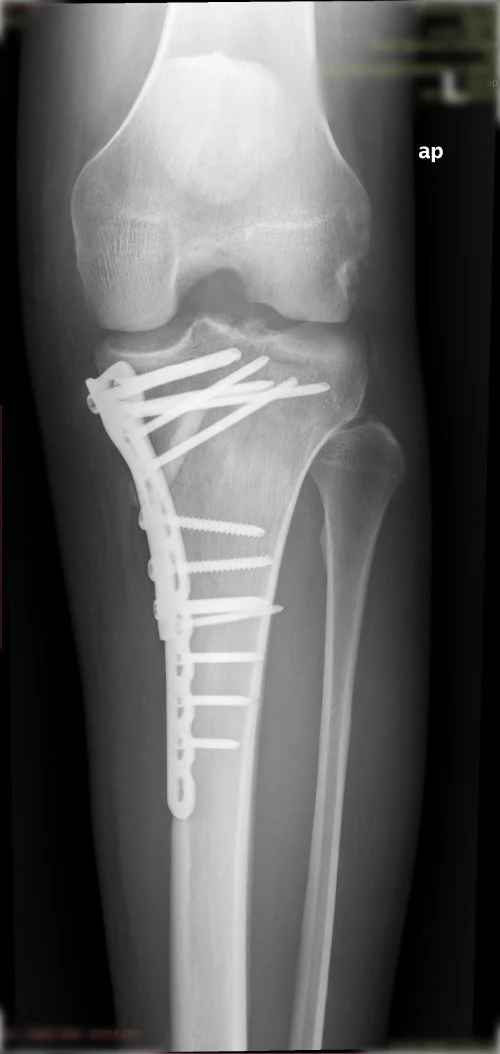

Görüntüleri büyütmek için resmin üstüne tıklayınız.